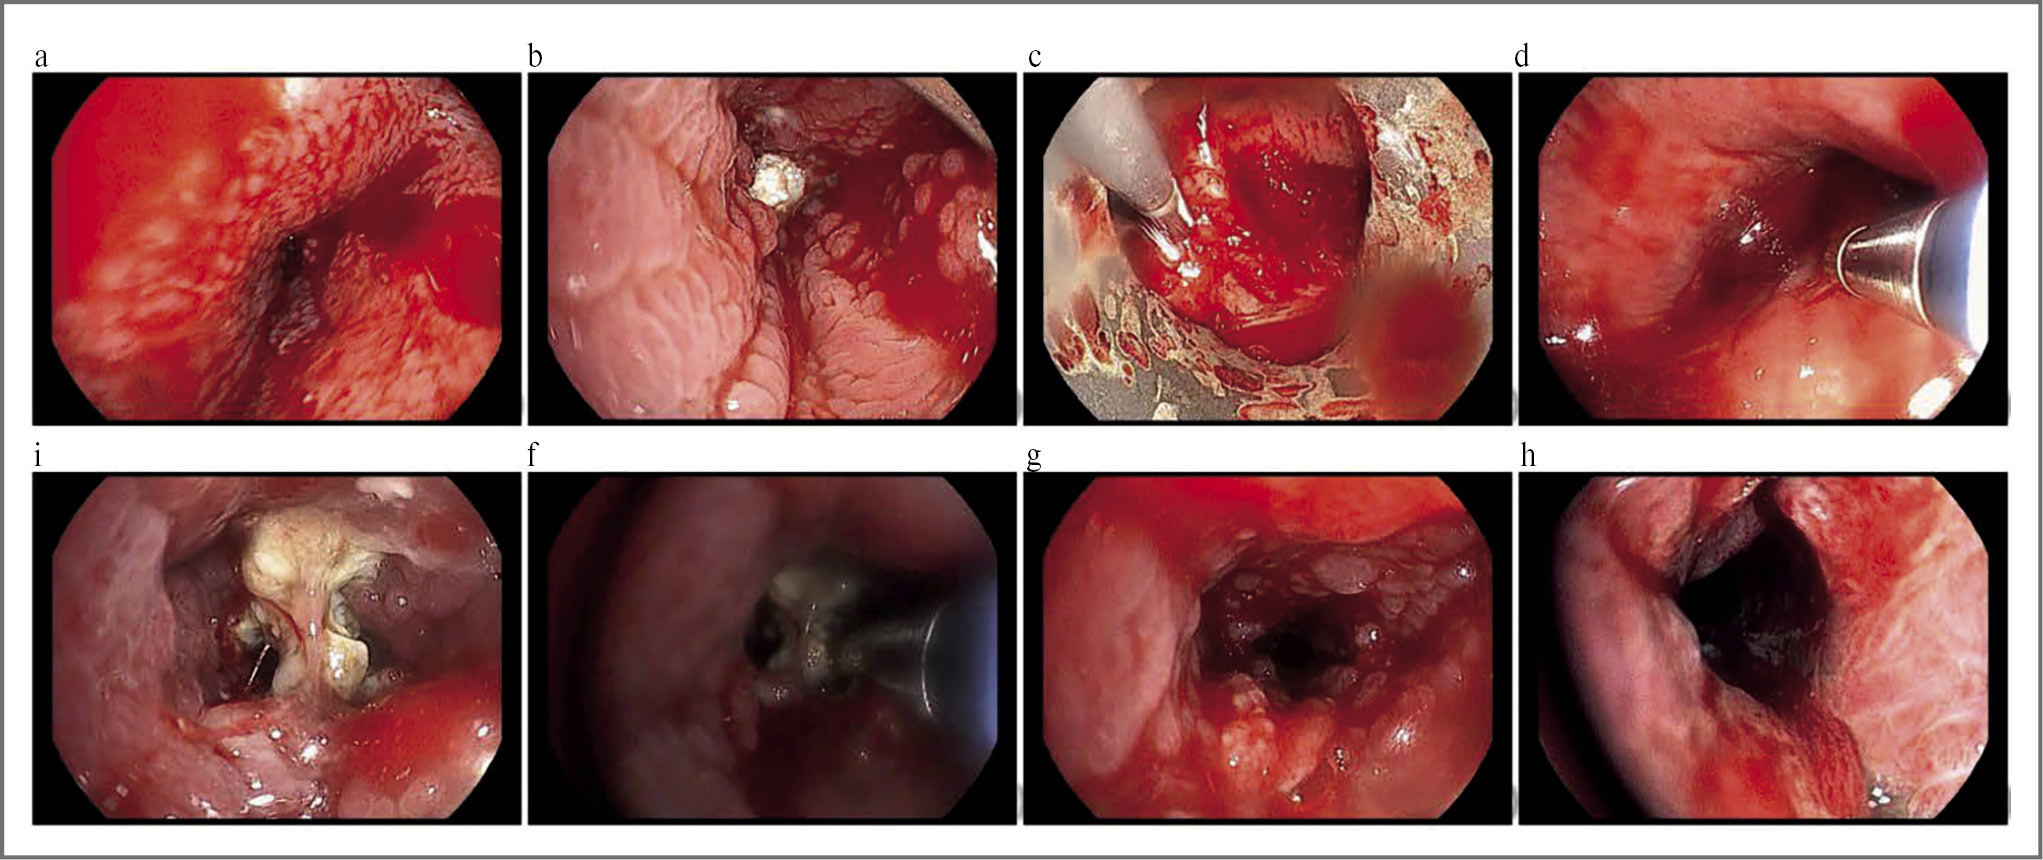

С учетом нивелирования значительной части инфильтративных изменений в зоне поражения и подозрения на наличие инородного тела совместно с заведующим отделением эндоскопии принято решение о выполнении повторной бронхоскопии с целью эвакуации обтуратора. 25.09.2020 пациенту выполнена бронхоскопия под наркозом, при которой отмечено уменьшение зоны пролиферативных изменений слизистой ТБД справа, достигнута визуализация инородного тела белого цвета и выполнена его криоэкстракция из промежуточного бронха (рис. 4, i–h).

Рис. 4. Видеобронхоскопия высокой четкости пациента П. Эндофото первичного исследования (а–d), а также исследования в динамике (d–h), видеобронхоскоп Pentax EB15 J10, видеосистема DEFINA: а – перибронхиальный стеноз устья правого главного бронха с признаками поражения слизистой; b – в дистальной трети правого главного бронха определяется множественная исчерченность слизистой, пролиферативные изменения, некротическая «шапочка», закупоривающая дистальную часть бронха; c – момент выполнения ригидной игловой биопсии средостения; d – эндобронхиальная криобиопсия изменений слизистой правого главного бронха; i – осмотр в динамике после курса терапии – в просвете промежуточного бронха определяется инородное тело (кость); f – момент выполнения криоэкстракции инородного тела; g, h – восстановление просвета правого главного и промежуточного бронха после криоэкстракции инородного тела.

Fig. 4. Flexible HD videobronchoscopy. Upper row – primary investigation, lower row – consequent bronchoscopy with cryoextraction of foreign body.

Извлеченное из просвета бронха содержимое направлено на гистологическое исследование, где установлено, что инородное тело представляло фрагмент пневматизированной губчатой кости (наиболее вероятно, птичья кость).